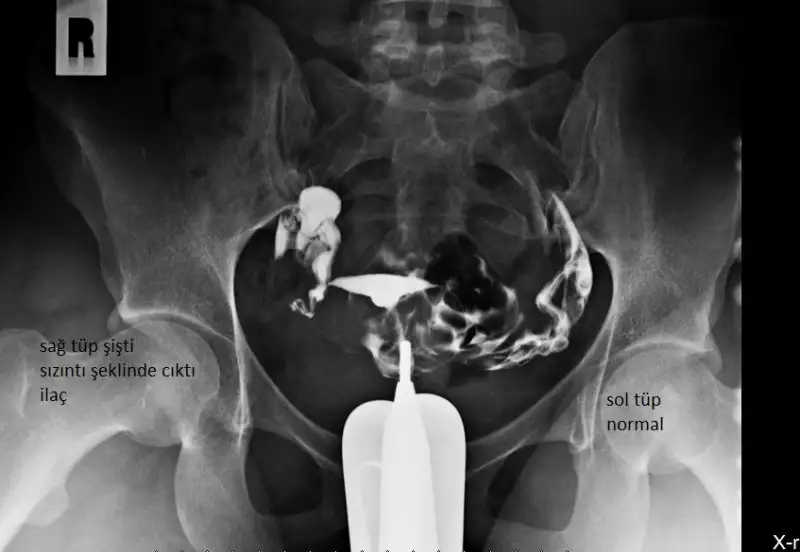

Hyr ancak rahm filminde görüluyor cnm